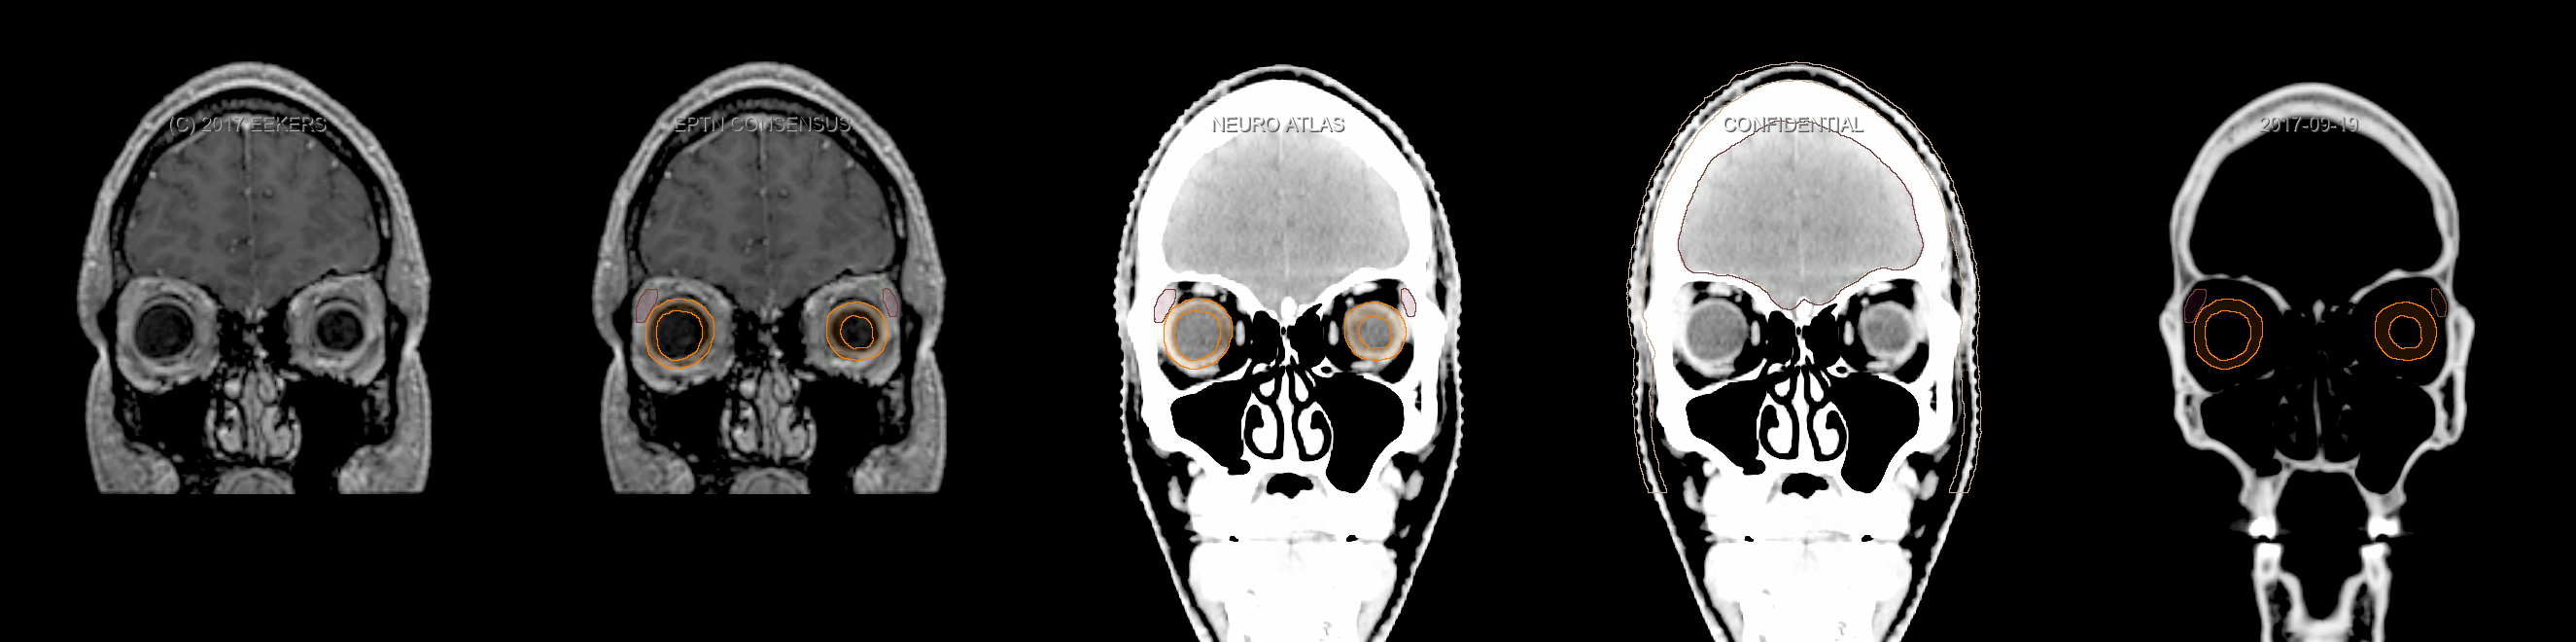

Eekers et al. have published an international neurological atlas for contouring of organs at risk in consensus with the European Particle Therapy Network (EPTN). The purpose of this consensus atlas is to decrease inter- and intra-observer variability in delineating OARs relevant for neuro-oncology. We propose this atlas is used in photon and particle therapy in order to derive consistent dosimetric data. When required this atlas will be updated according to new insights.

Included are all OARs known to be relevant for radiation-induced toxicity in neuro-oncology: brain, brainstem, cochlea, vestibulum & semicircular canals, cornea, lens, retina, lacrimal gland, optic nerve, chiasm, pituitary, hippocampus and skin. A new OAR relevant for neuro-cognition, the posterior cerebellum is also included.

Three-dimensional delineation of the fifteen consensus OARs for neuro-oncology are shown on CT and 3 Tesla (3T) MR images (slice thickness 1 mm with intravenous contrast agent). All are presented in transversal, sagittal and coronal view.

From left to right: MR without structures, MR with structures, CT (WW/WL 120/40) with structures, CT (WW/WL 120/40) with Brain and Brainstem Surface, CT (WW/WL 1500/120)with structures